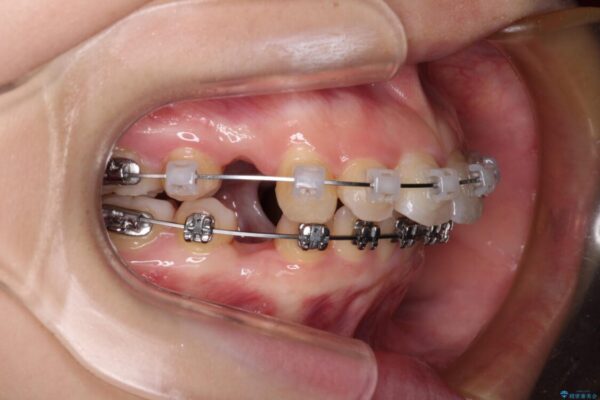

治療途中

• 【モニター】口が閉じられない ワイヤー装置での抜歯矯正 治療途中画像

上下前歯が著しく前突している状態であったので、上下左右の第1小臼歯4本を抜歯し、ワイヤー装置にて矯正治療を行うこととしました。

舌の突出癖により、前突になったと考えられたため、舌のトレーニングをしっかりと行うよう指導しました。

※写真にある上顎装置はメタルブラケットではありません。メーカー在庫都合などにより別の装置を使用しております。